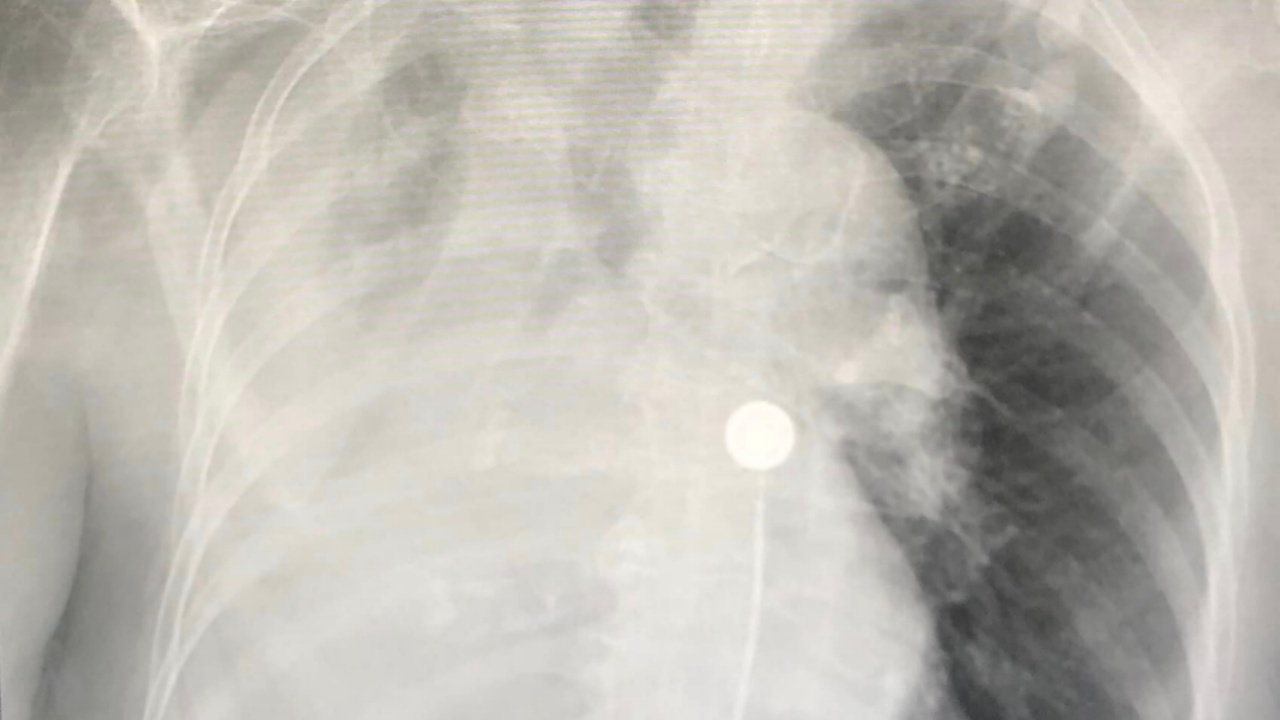

มาโรงพยาบาลวันที่ 9 พฤษภาคม 2566 ด้วยอาการไข้และเหนื่อย 2 วัน ระดับออกซิเจนที่ปลายนิ้วปกติ 98% ผล ATK บวก เอกซเรย์ปอดมีฝ้าขาวที่ปอดขวาด้านล่าง (ดูรูป)

วินิจฉัยเป็นปอดอักเสบจากการติดเชื้อไวรัสโควิด ให้ยาเรมเดซิเวียร์เข้าทางหลอดเลือด คนไข้มีเสมหะมาก เหนื่อยมากขึ้น ระดับออกซิเจนต่ำ ต้องย้ายเข้าห้องไอซียู ให้ออกซิเจนชนิด Hi-Flow เอกซเรย์ปอดซ้ำ เห็นปอดข้างขวาแฟบทั้งข้าง (ดูรูป)

ญาติปฏิเสธใส่ท่อหายใจเพราะอายุมากแล้ว ได้ทำการส่องกล้องเข้าไปในหลอดลมเห็นเสมหะสีขาวขุ่นเหนียวข้นปริมาณมากจนอุดตันหลอดลมด้านขวา หลังดูดเสมหะ เอกซเรย์ปอดดีขึ้น (ดูรูป) ให้ยาปฏิชีวนะร่วมด้วย คนไข้ดีขึ้นชั่วคราว ต่อมาปอดข้างขวาก็แฟบอีก (ดูรูป) อาการแย่ลง เสียชีวิตในที่สุด